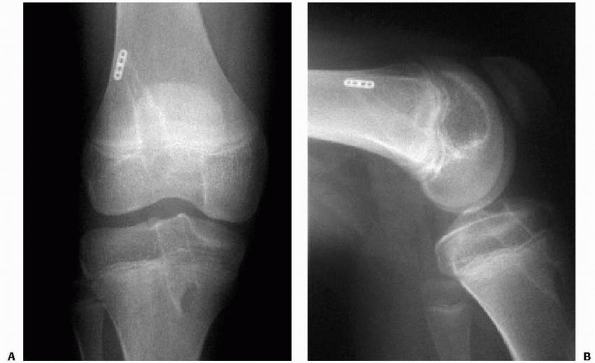

FIGURE 24-10

Type III tibial spine fracture in an 11-year-old male child treated with arthroscopic reduction and 3.5-mm cannulated screw fixation. Preoperative anteroposterior (A) and lateral (B) radiographs. Postoperative anteroposterior (C) and lateral (D) radiographs. |